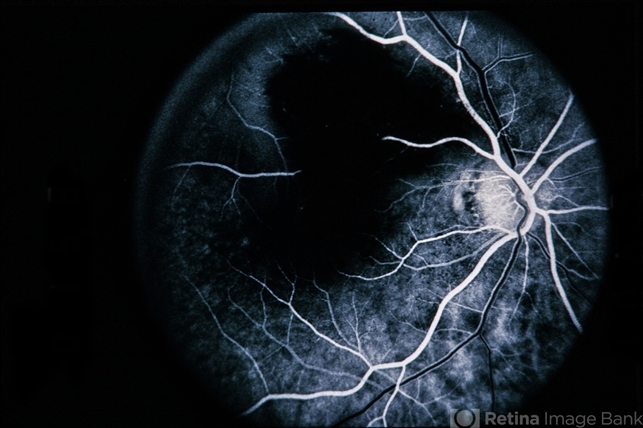

branch retinal vein occlusion (BRVO)

Female patient with BRVO.